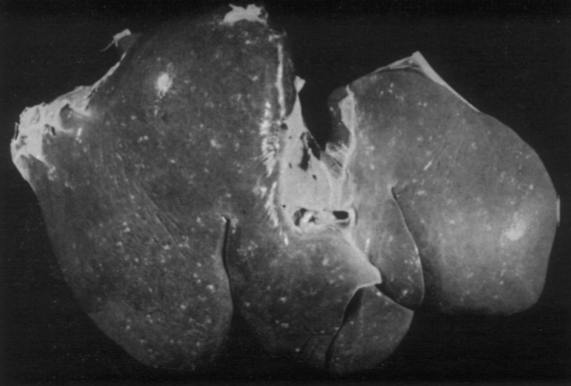

If this is a liver of a horse, what parasite is responsible?

Parascaris equorum